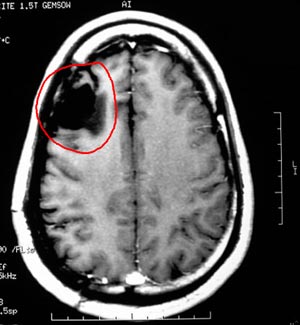

Figura 92 - Ressonância nuclear magnética de encéfalo mostrando a lesão junto à área motora no hemisfério cerebral direito.

Figura 96 - Ressonância nuclear magnética de encéfalo antes da cirurgia revelando a cavidade da cirurgia prévia